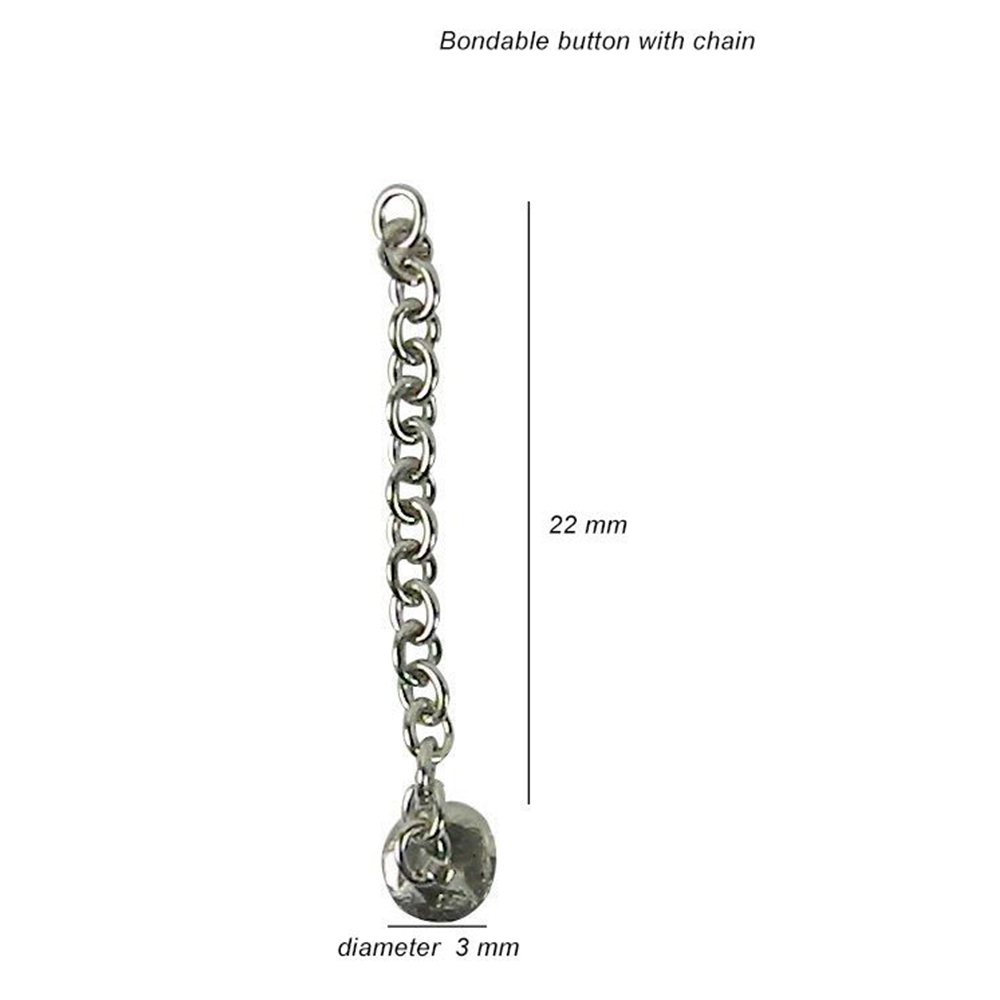

- Lingual Bondable Buttons with Chain: These buttons come with a built-in chain attachment. They are convenient for connecting to various orthodontic accessories, such as elastics or power chains.